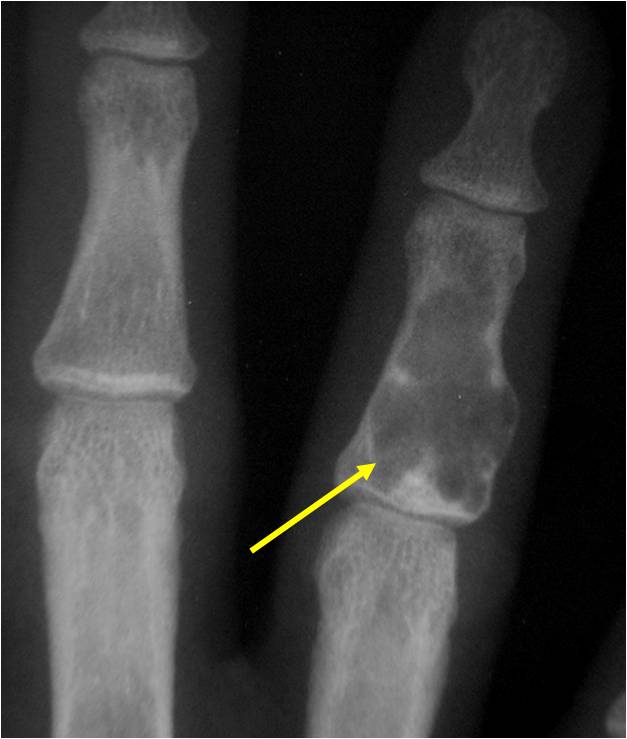

- Localized, radiolucent defect usually with punctate calcifications

- Calcifications are typical but not always present

- Matrix may demonstrate various degrees of calcification

- Calcifications are stippled, punctate, popcorn like calcifications and “Ring and Arc” calcifications

- Cartilage tumors grow in a lobular manner. The perimeters of the lobules undergo

- enchondral ossification that may calcify. If the entire perimeter of the lobule calcifies it appears

- radiographically as a “Ring”. If a portion of the perimeter of a lobule calcifies it forms an “Arc” on

- an X-ray.

- Cortex may be scalloped and thinned in the phalanges

Plain X-Ray:

- Geographic lytic lesion

- Central often metaphyseal in long bones

- Expansile remodeling with thinned cortex

- Chondroid matrix with calcifications in majority of tumors

- Approximately 20% have limited or no calcifications

Geographic lesion Stippled calcifications in lesion Phalanx is expanded Significant endosteal scalloping No cortical destruction No soft tissue extension Cortex Scalloped and Expanded